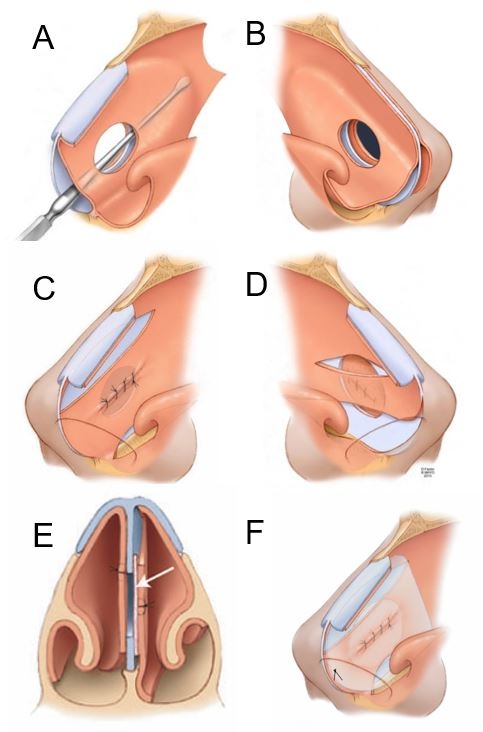

Perforation repair basic technique: Perforation length, height, and distance from the anterior perforation margin to the nasal valve angle and columella are recorded. The fundamental steps in our bilateral flap and graft repair are illustrated in Figure 1. Endoscopic photos of the left side closure are presented in Figure 2. Perforation repair is performed through a right hemitransfixion incision[13]. Mucoperichondrial/periosteal elevation proceeds on the left side through the incised circumference of the perforation margin and then superiorly towards the junction of the upper lateral cartilage (ULC) and septum. Mucosal elevation then proceeds inferiorly and laterally onto the nasal floor as determined by perforation size and position. For larger perforations, the elevation proceeds 2 cm posterior to the posterior margin. Mucosal elevation is then performed on the right side, extending through the perforation and then inferiorly and laterally onto the nasal floor. Elevation superior to the perforation’s superior margin on the right side is avoided. Flap development is first performed on the left side to accomplish complete and tension-free defect coverage. A superior bipedicled advancement flap is developed and, if necessary, an inferior bipedicled flap. The superior flap incision may start anterior to the internal valve angle as determined by perforation size and position. The incision arcs above the perforation and then for 2 cm beyond the posterior margin for larger defects to allow for flap release and advancement. Mucosa from the undersurface of the ULC can be incorporated into this flap through an intercartilaginous incision for larger perforations. The incision for the left inferior flap is made with cautery anterior and inferior to the head of the inferior turbinate. Submucosal elevation proceeds over the piriform aperture to connect to the prior elevation of nasal floor mucosa. The mucosal flap incision is made with a scissors or monopolar cautery, starting laterally at the nasal floor-inferior meatus junction and ending posteriorly at the septum-floor of nose junction 2 cm posterior to the perforation. Anteriorly, sharp undermining dissection through the hemitransfixion incision disrupts the fibrous elements binding mucosa to the nasal spine and premaxilla to allow for flap release and advancement. Superior and inferior flaps are advanced and the collapsed mucosal margins sutured with interrupted 4-0 chromic sutures on a Castroviejo needle holder with a P-3 needle slightly bent to tighten the rotation arc. Suturing of the superior margin of the superior flap to the defect’s superior cartilage margin is performed for flap stabilization when the overlap is tenuous. Attention is then directed back to the right side. A bipedicled advancement flap comprised of mucosa inferior to the perforation and adjacent nasal floor is developed. The hemitransfixion incision is extended posterolaterally onto the nasal floor and then medially to the floor-septum junction posterior to the perforation. This inferior flap is advanced superiorly over the defect to oppose the left suture line closure and support of the interposition graft. A superior flap is not developed for advancement on the right side to avoid bilateral compromise of superior septal cartilage vascularity and the risk of re-perforation. Septal deformities are addressed next, followed by the application of an autologous tissue (temporalis fascia, septal cartilage/bone, or auricular perichondrium) interposition graft. The repair is covered with thin 0.02 in soft polymeric silicone sheeting secured with a single nylon suture placed anteriorly and bolstered with folded pads of Telfa gauze. The packs are removed on postoperative day 2 and the sheeting in 10-14 days [Figure 3]. Frequent saline spray moisturization and ointment lubrication are recommended for 6 weeks post pack removal, and then as indicated for persistent dryness or crusting.

Figure 1. Illustrations of bilateral mucosal flap closure. (A) Extent of septal mucosal elevation on the left side; (B) Elevation superior to the perforation is avoided on the right side; (C) Superior and inferior flaps are advanced and sutured together for a tension-free closure on the left side; (D) The right inferior bipedicled flap is advanced to oppose the left-sided suture line and support the interposition graft; (E) An interposition graft is placed within the septal space to complete the perforation repair; (F) Repair is covered bilaterally with silicone sheeting.